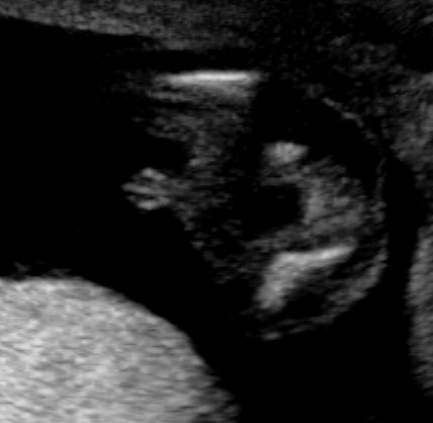

Tech said boy! Think so?

Can you ladies help please? This is my 20 weeks scan. Tech said it's 90% boy as she can see penis. Do you ladies think so? She did not point out the parts to me. And when I look at these pics, I think it's the boy bits I am looking at, but I am not too sure???

THe first pic looks like a boy for sure. COngrats :)